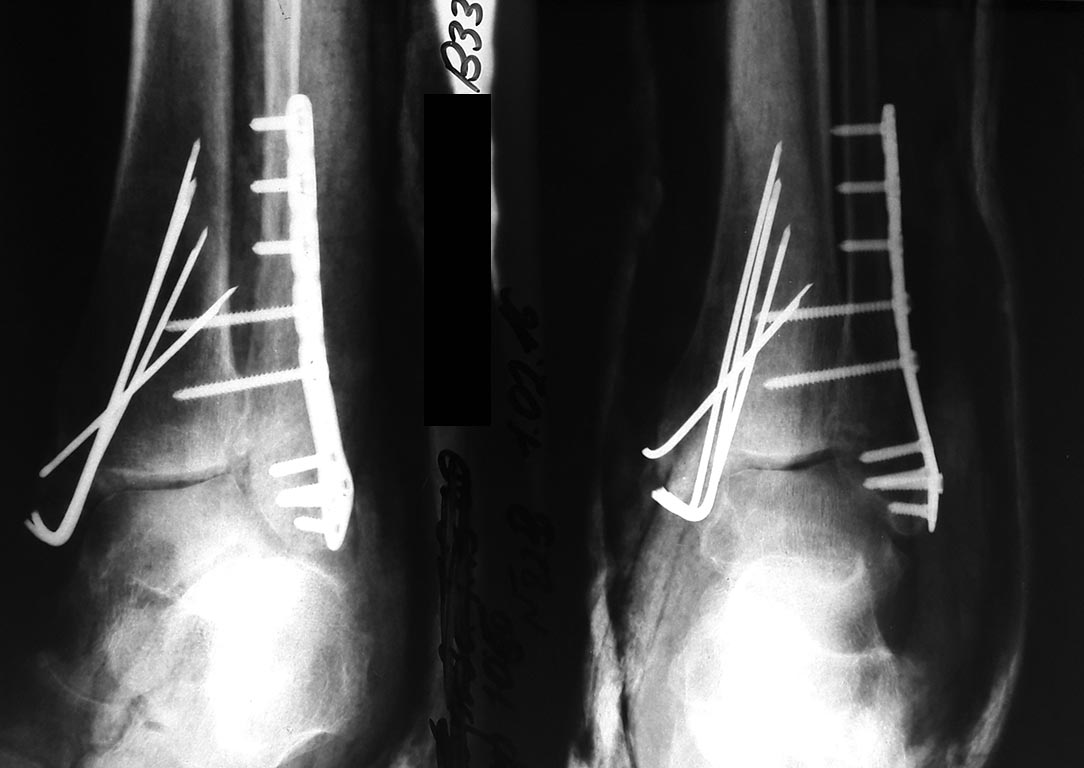

Вопрос изначально про клин. рекомендации был. Собственно предмет разбиральства это другая тема. Тем не менее: больная, 36 лет после застарелого перелома лодыжек, >3 месяцев, поступила "по знакомству". В 1-2016. Выполнена остеотомия наружней лодыжки, синтез пластиной с латеральным расширением ( компании МТК). Позионирование дмс и синтез внутренней лодыжки. Фото. Через 6 мес. - удаление мк. Фото после удаления нет и не было. Доктор не счел нужным. Больная периодически доктором консультирована после выписки. После из поля зрения выпала. "Всплыла" уже ввиде претензии письменной, в которой указала повторную реконструкцию в Приорова той же самой пластиной. Снимков не предоставлено. Видимо будут при экспертизе или в суде... Сумма в претензии 175т. руб. включая транспортные расходы. В кратце так. Клин. рек. нужны для защиты что все было сделано правильно. Есть еще вопрос к м.к. Она ее приобрела. Ну и якобы доктор лечащий утверждает что имевшимися у нас 1\3 УС Остеомед синтез провести было бы не корректно из-за застарелого перелома. Еще и за это приобретение в претензии зацепка. Поэтому клин.рекмендации потребовались. Видимо это разбирательство ближайшего времени.

Рентгенограммы 2016

Сергей, если на суде в качестве доказательства свой правоты -не только в тактике, но и в исполнении лечения, вы покажете эти снимки, то с большой долей уверенности можно предположить, что пациентка выиграет иск без особого труда.

Но, вот достигнутая, а в данном случае, точнее -не достигнутая репозиция, это вполне может быть предметом для иска, + отсутствие снимков в правильных, типичных проекциях (и без гипса) наводит на мысль, что хирург мог быть также не очень щепетильным в выполнении анатомичной (чего требуют все руководства) репозиции. Понятно, что снимки делал не хирург, а рентгеновский техник, но и это техник, и врач рентгенолог и даже хирург (и его заведующий) приняли эти снимки. Т.е. в общем-то, всем на все наплевать.

Очень сложно будет защищаться, особенно если снимки после ревизии окажутся просто более качественными и выполненными в стандартных проекциях, даже если с репозицией не стало лучше.... Хотя "тактика", вероятно, была правильной